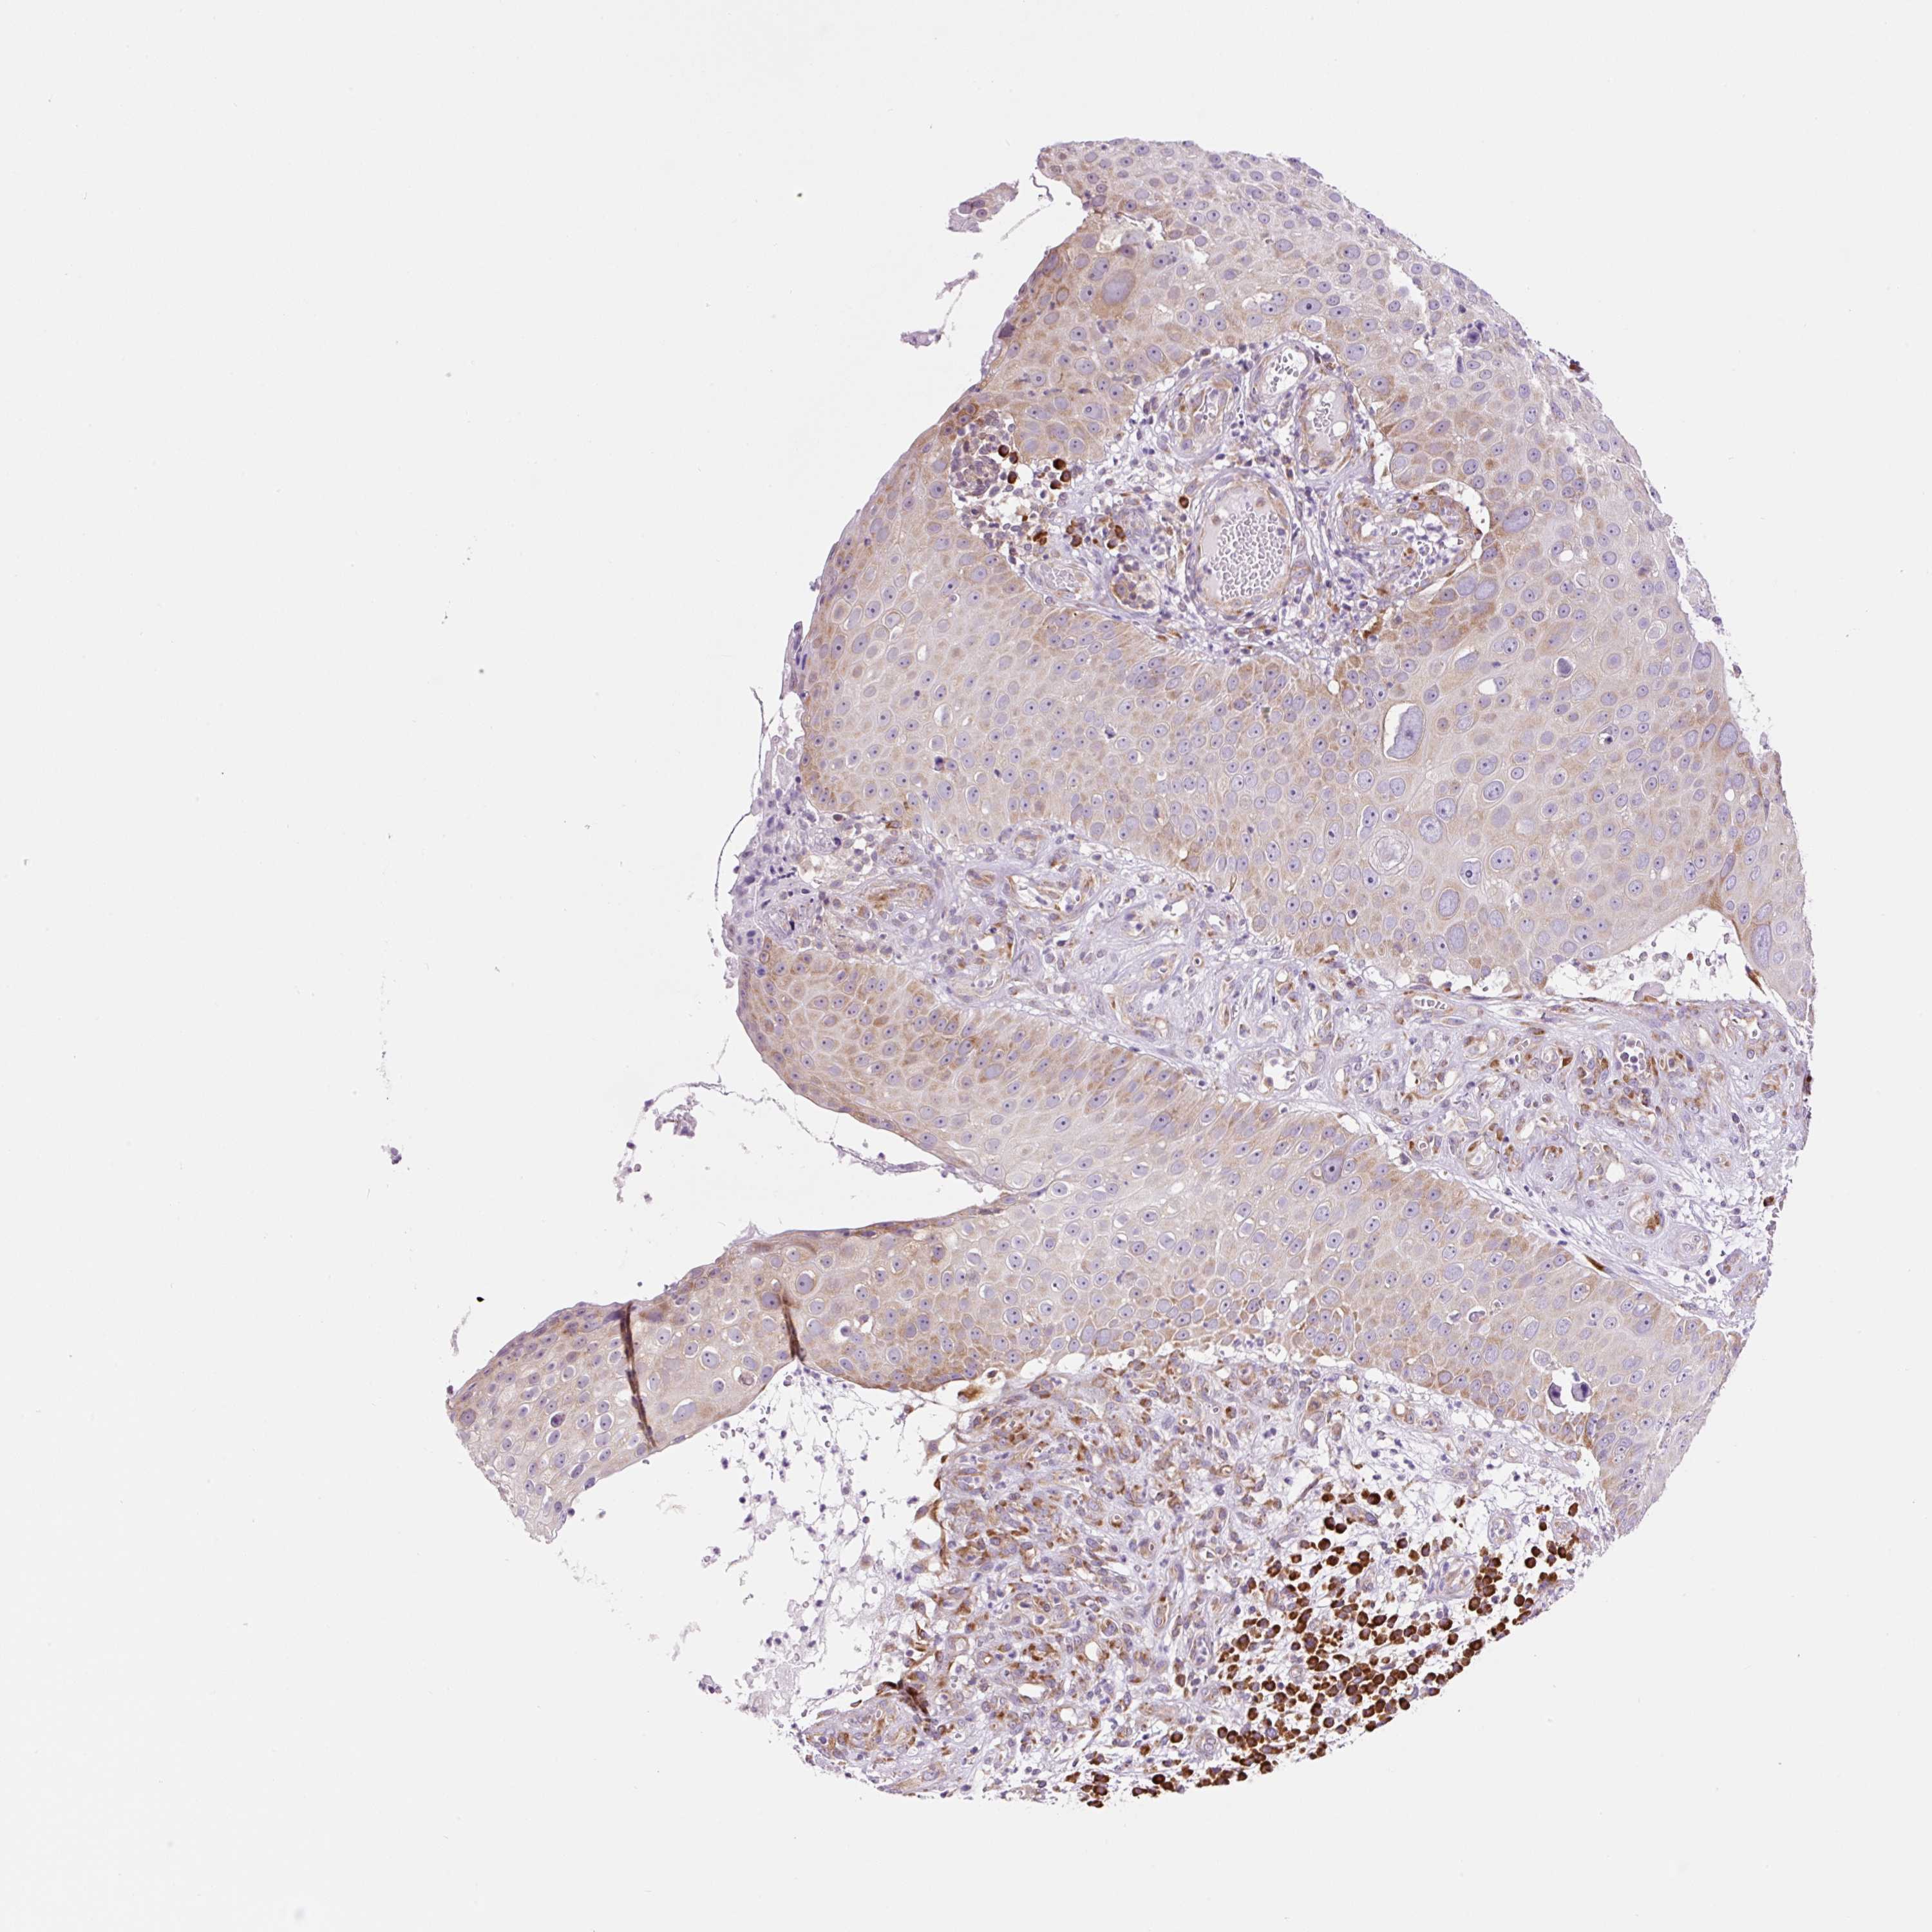

Basal cell and squamous cell cancer

SKIN CANCER - Protein expressioni

A mouse-over function shows sample information and annotation data. Click on an image to view it in a full screen mode. Samples can be filtered based on level of antibody staining by selecting one or several of the following categories: high, medium, low and not detected. The assay and annotation is described here.

Antibody stainingi

Antibody staining in the annotated cell types in the current human tissue is reported as not detected, low, medium, or high, based on conventional immunohistochemistry profiling in selected tissues. This score is based on the combination of the staining intensity and fraction of stained cells.

Each image is clickable and will lead to virtual microscopy that enables deeper exploration of all samples and also displays staining intensity scores, fraction scores and subcellular localization as well as patient and tissue information for each sample.

Antibody HPA053169

Staining

Medium

Strong

>75%

Location

Cytoplasmic/membranous,nuclear

Squamous cell carcinoma, NOS

Squamous cell carcinoma, metastatic, NOS